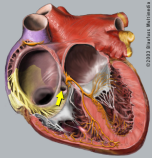

Ablation carries a high success rate, invovling lines placed in the narrow corridor between the tricuspid valve and inferior vena cava.